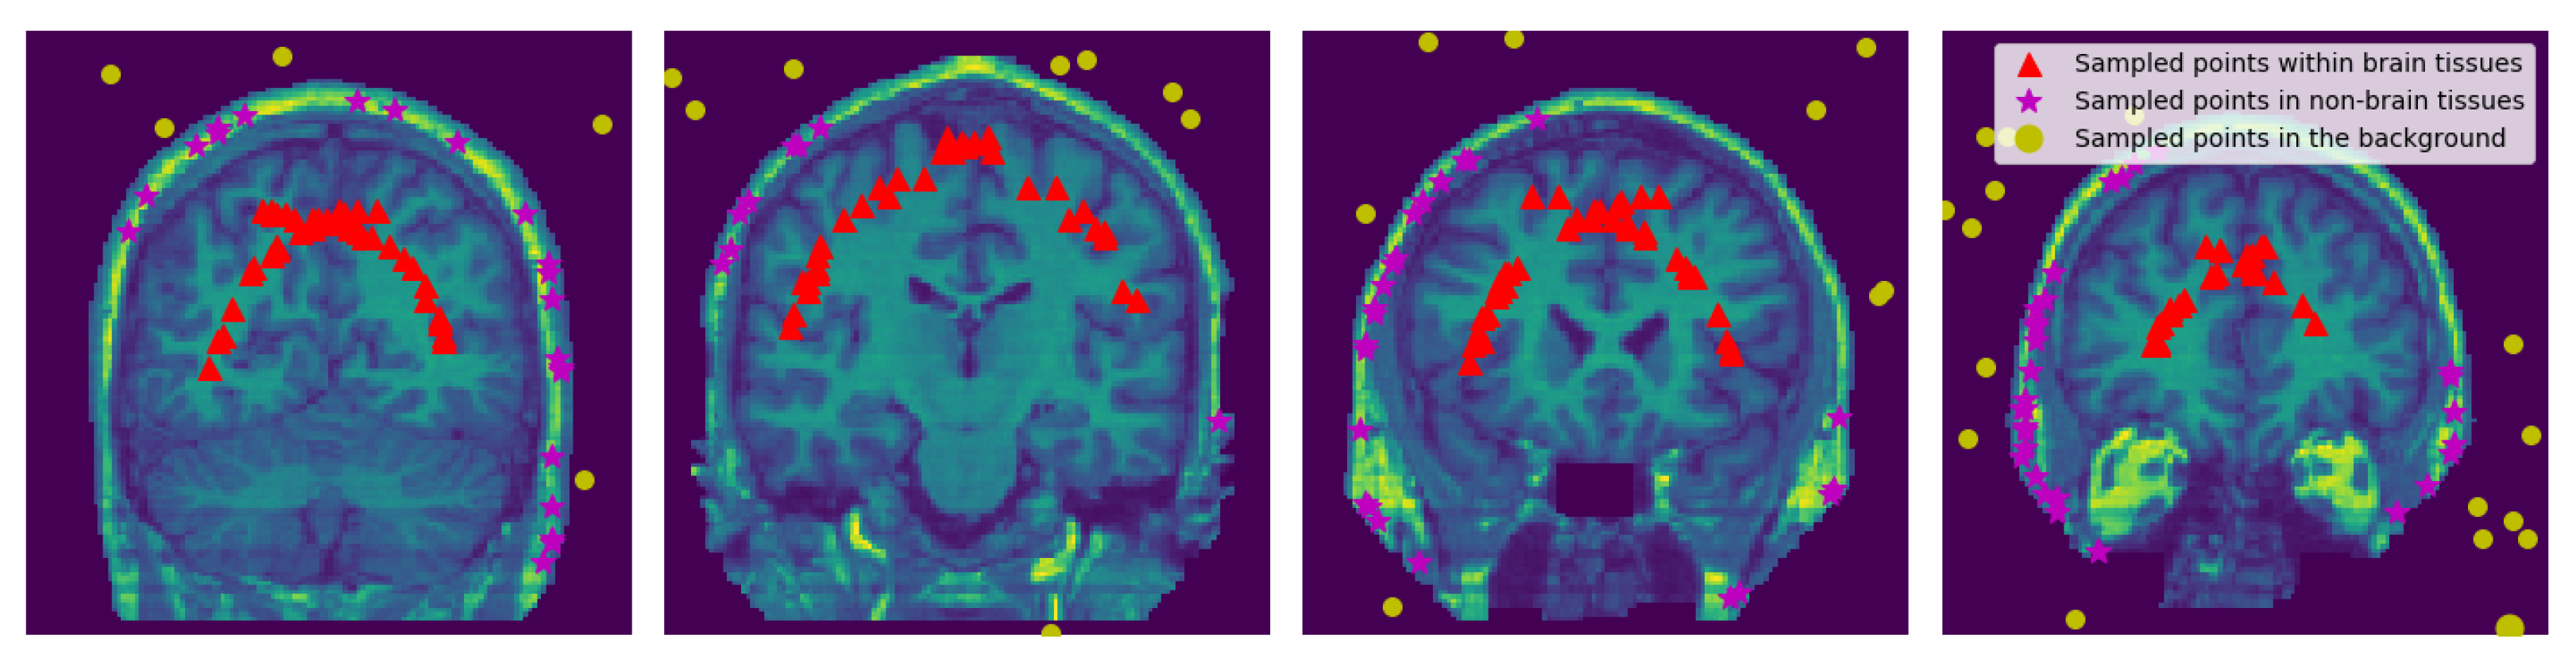

To obtain points in the non-brain tissues we use all the discrete 3D edge-like points distributed at the surface of the head and pull them inside towards the non-brain tissue by . The pulled points are rechecked if there is any point with the intensity value of zero it is removed. See Figure 4 and Figure 5.

Figure 4.

Sampled Points: 2D visualization of the representative coronal section from MRI image of a single subject (OASIS data) showing the sampled points within the brain, within the non-brain, and in the background region. and values were set to 15 and 3, respectively.